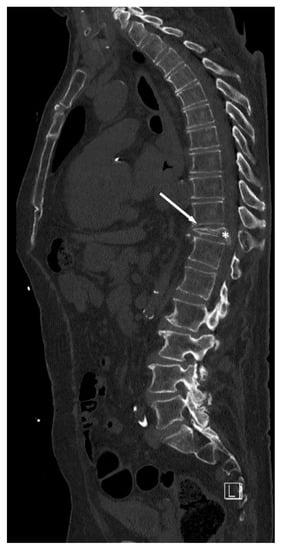

4. Ewing’s Sarcoma

- Kager, L.; Zoubek, A.; Kotz, R.; Amann, G.; Wiesbauer, P.; Dobrowsky, W.; Gadner, H. Vertebra plana due to a Ewing tumor. Med. Pediatr Oncol. 1999, 32, 57–59. [Google Scholar] [CrossRef]